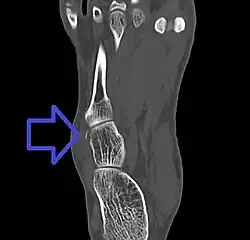

A cuboid fracture is a fracture of the cuboid bone of the foot. Diagnosis is by X-ray imaging, magnetic resonance imaging, or bone scan.[1] Treatment may be conservative or involve surgery, depending on the type of fracture.[1] They are rare.[1]